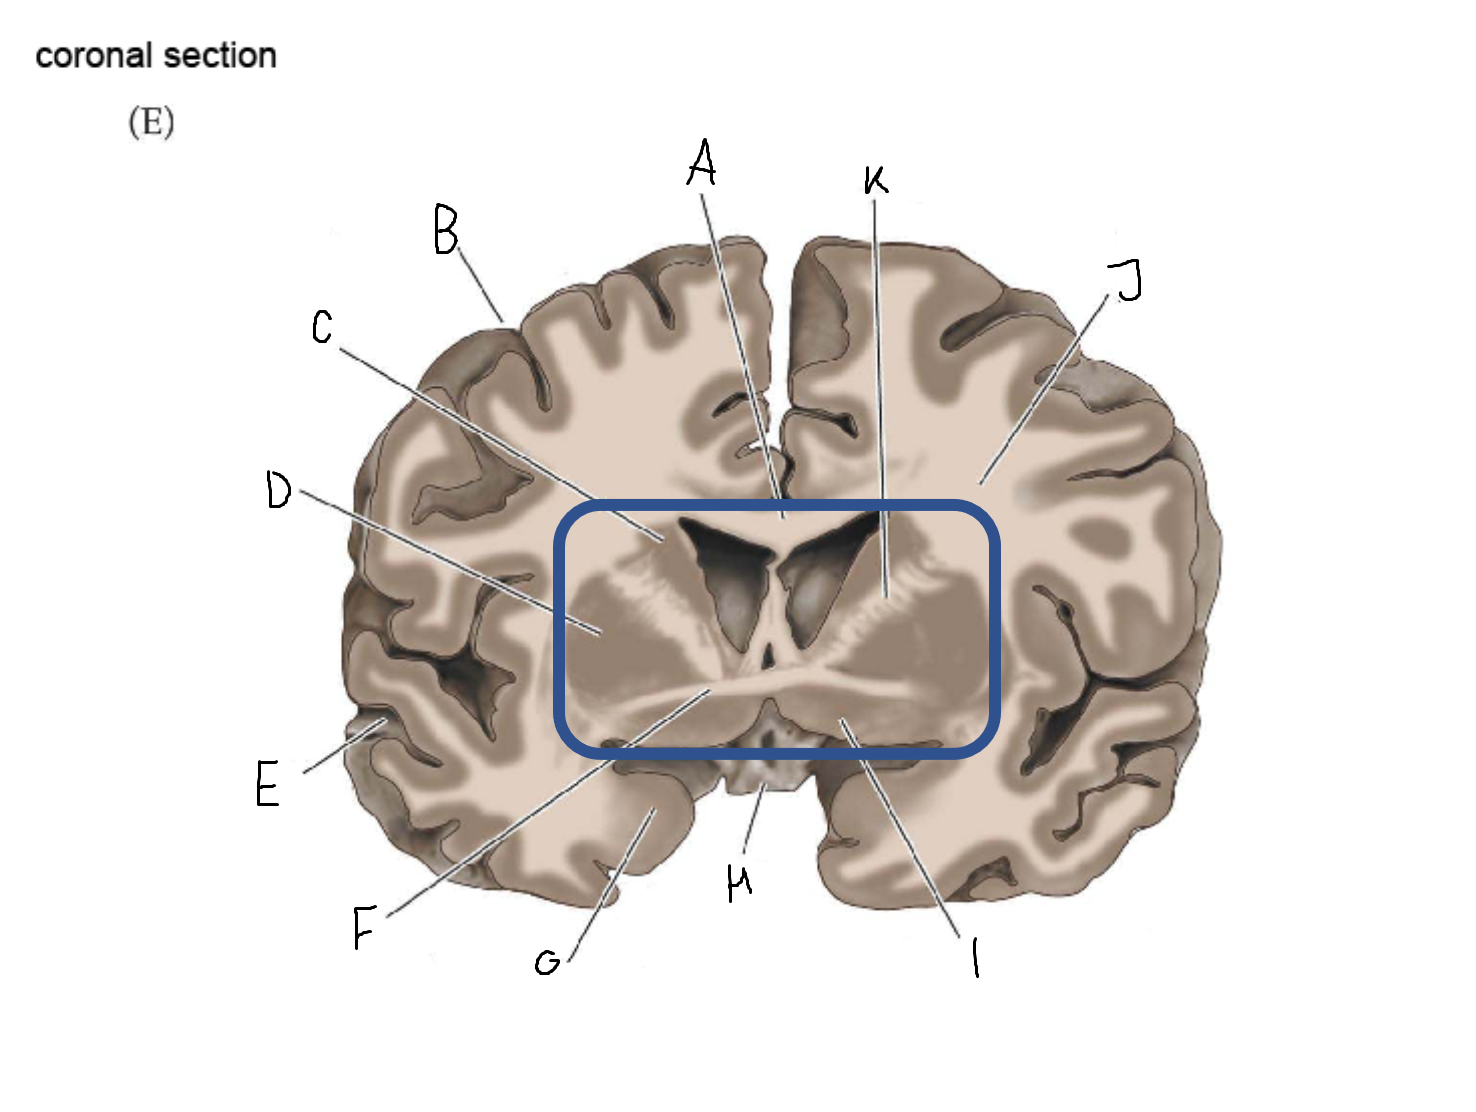

B

anterior horn of lateral ventricle

C

head of caudate nucleus

D

internal capsule (anterior limb)

E

putamen

F

globus pallidus

G

Thalamus

H

External capsule

I

internal capsule (posterior limb)

J

tail of caudate nucleus